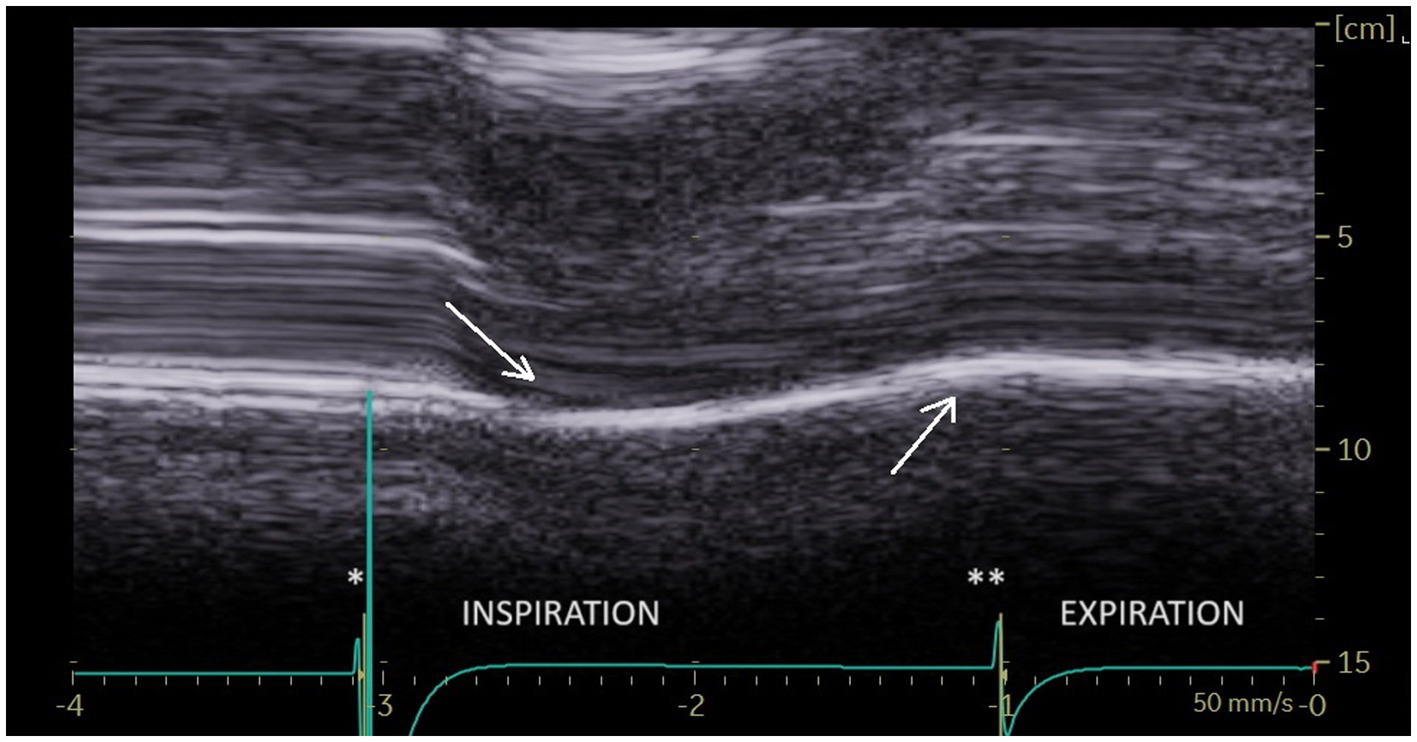

During deep inspiration, most patients (86%), showed a biphasic movement of the paralyzed hemidiaphragm, with an initial paradoxical cranial movement and a terminal caudal displacement (Figure 6). The caudal displacement could either be absent or reach more than 2 cm. This kinetics has previously been reported by Patel et al. (27) and Boussuges et al. (25).

Figure 6

During deep breathing a biphasic movement was observed with an initial paradoxical movement (first arrow) and a terminal caudal displacement (second arrow). *Beginning of inspiration. **Beginning of expiration.